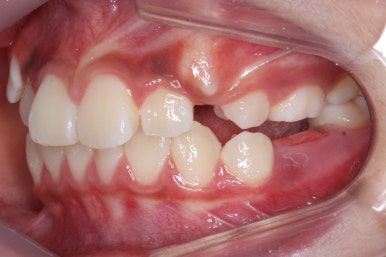

초진 시의 모습입니다.

해당 환자분은 영구치가 아직 모두 나오지 않았지만 서둘려 교정을 시작한 이유는 2급 부정교합에 약간 가까웠기 때문입니다.

2급 부정교합은 아래턱이 작아 위치가 뒤에 있다거나 위턱이 반대로 커서 앞에 있는 경우로 상대적으로 입이 튀어나와 보이게 하며 아래턱은 무턱처럼 보이게 합니다.

골격분석과 X-ray 등으로 확인했을 때, 이번 환자분은 위턱이 약간 상대적으로 나와있다고 판단이 되었습니다. 위쪽 치열은 아래쪽 보다 앞으로 나와있으며 특히 어금니가 앞쪽으로 나와있었어요.

따라서 교정계획은 헤드기어를 사용해 위쪽 어금니는 뒤로 밀고 영구치가 추후 맹출이 될 때 까지 시간을 주자는 것이였어요.